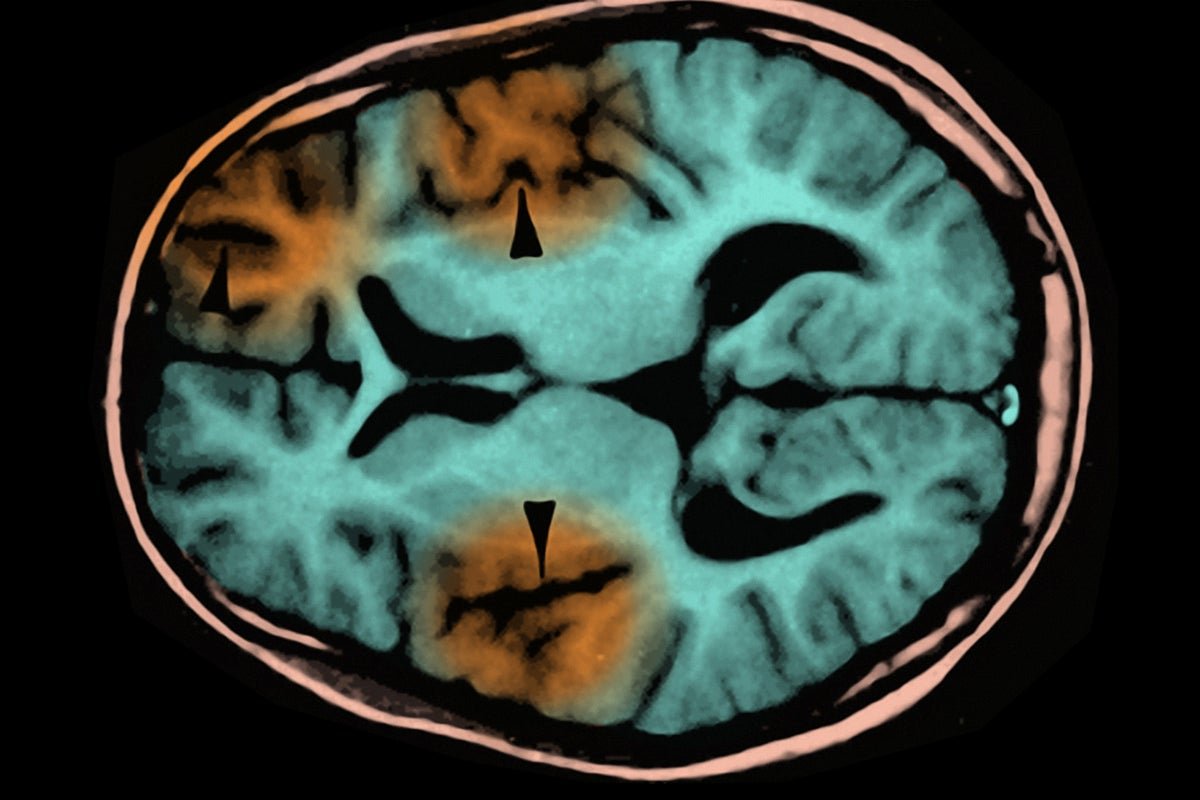

An MRI scan showing subacute sclerosing panencephalitis, a complication of measles infection.

The child who died suffered from subacute sclerosing panencephalitis (SSPE), a progressive brain disorder that usually develops two to 10 years after a measles infection. The measles virus appears to mutate into a form that avoids detection by the immune system, allowing it to hide in the brain and eventually destroy neurons.